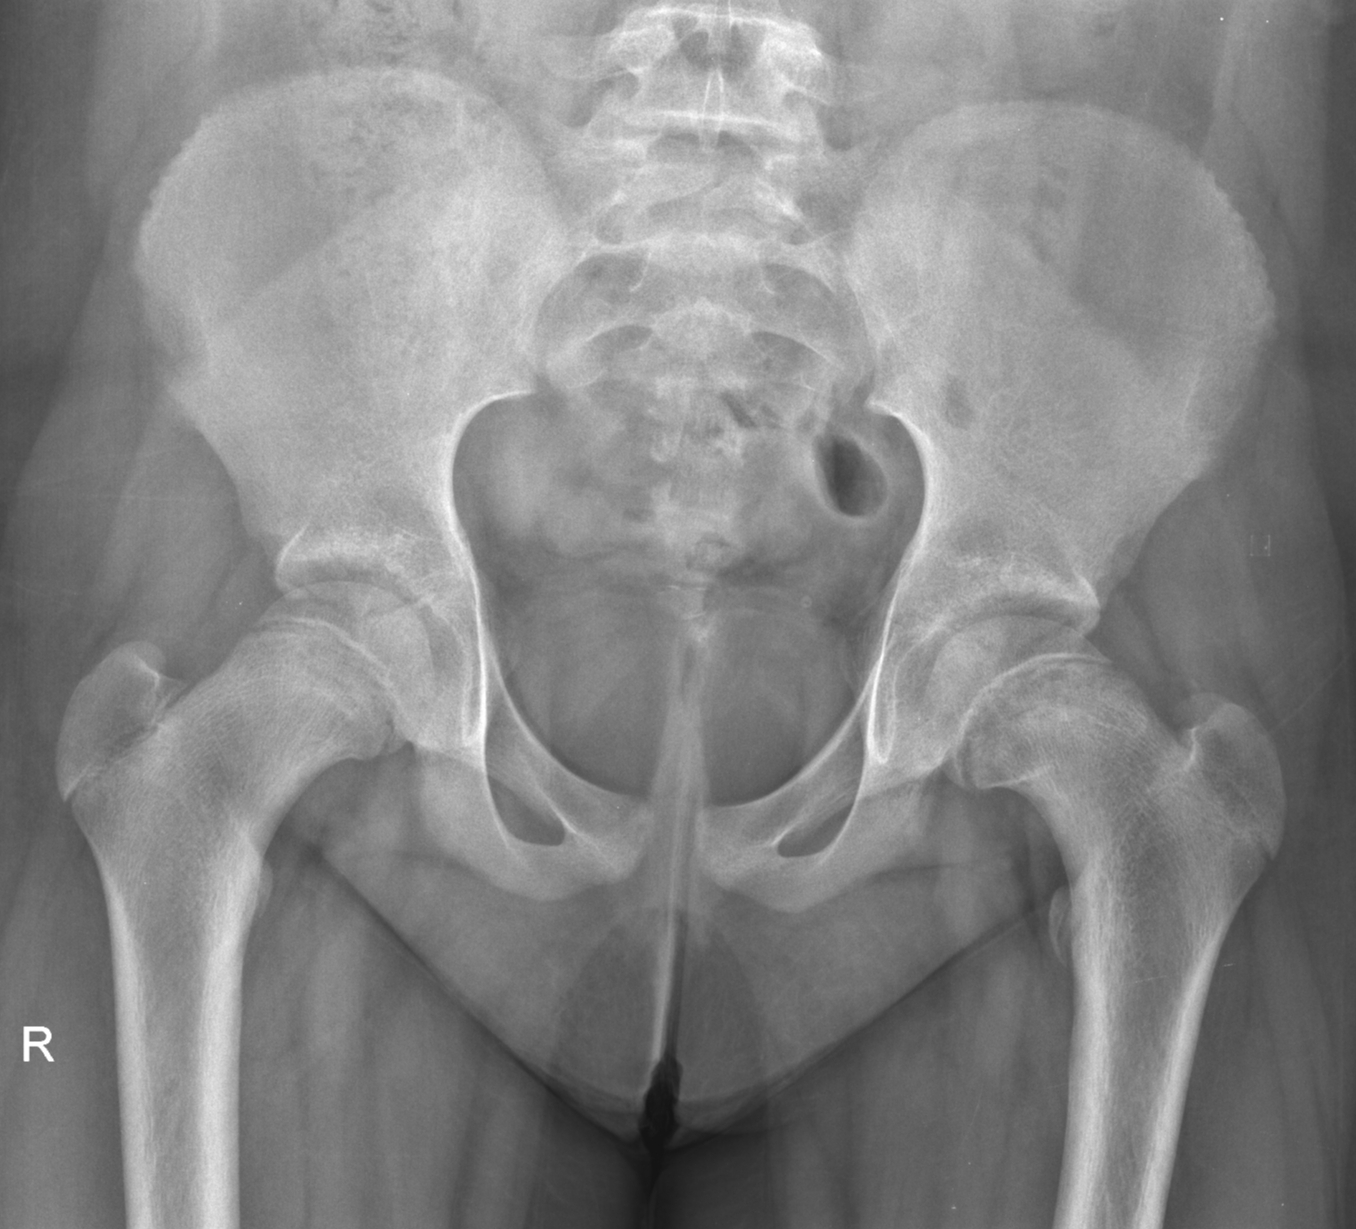

CASE 3

HISTORY

13 year old girl. Bilateral hip pain for 3-4 weeks. Difficulty in weight bearing.

QUESTION

Concentrate on the hip joints. Are both hips normal?

RADIOGRAPHS

ANSWER